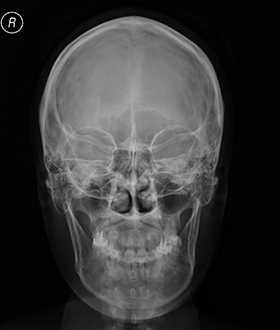

Рентгенография черепа и позвоночника: изображение и диагностика